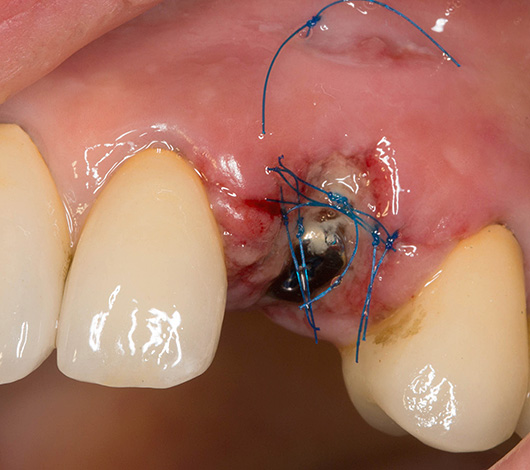

Talvez também seja importante mencionar a divergência de suturas, frequentemente aplicada à ferida após o implante. A foto abaixo mostra um exemplo do estado normal das suturas imediatamente após a cirurgia:

A divergência das suturas, como complicação, quase nunca é sinal de implantes dentários mal sucedidos, pois caracterizam mais o resultado do comportamento da própria pessoa. As violações podem ser muito diferentes: desde a não observância dos princípios de higiene bucal e ignorando as recomendações do médico, até o "toque" não autorizado na cavidade oral com dedos, palitos de dente, etc., o que leva a danos mecânicos nas suturas ou contribui para o início do processo inflamatório. Isso provoca a divergência de costuras no futuro.